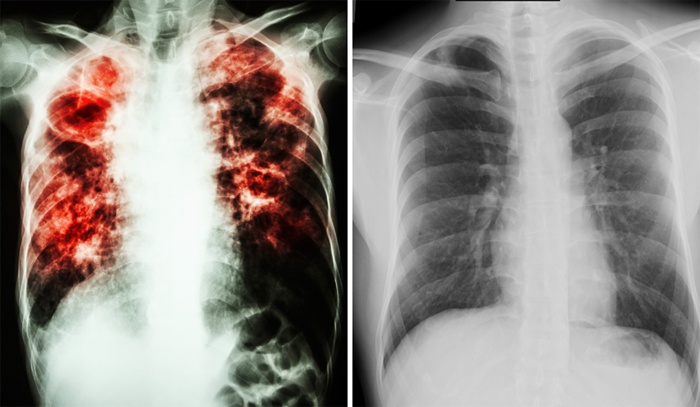

ФОТО З РОЗШИРЕНОГО ПОШУКУ У зоні проведення операції Об’єднаних сил (ООС) можлива екологічна катастрофа й епідемія туберкульозу,…

Ознаки звичайної застуди можуть сигналізувати про серйозні хвороби з летальним результатом. Висока температура, біль у горлі, нездужання…